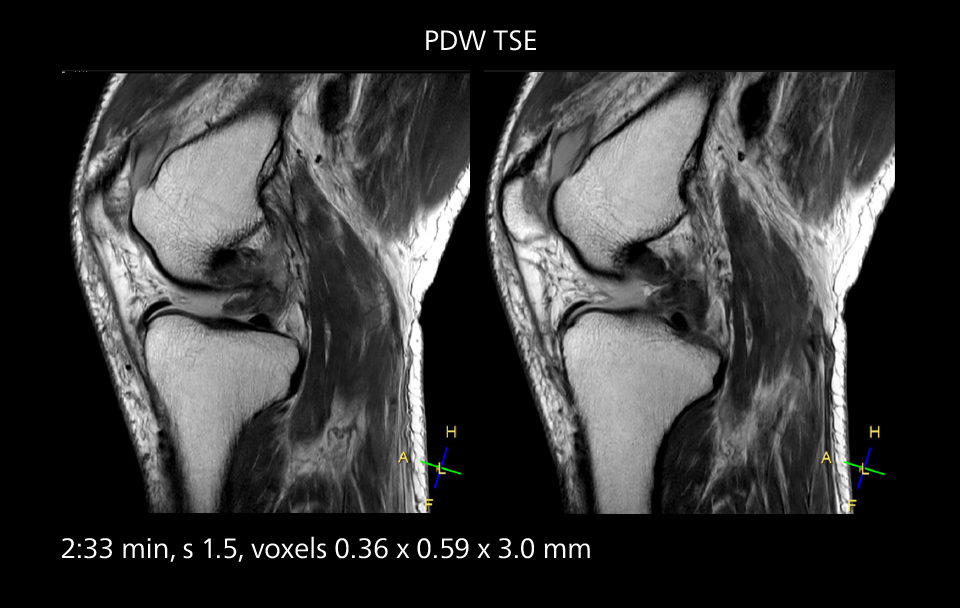

An example of increased imaging speed is in knee studies. “There is a definite scan time reduction for T2* mFFE and proton density TSE – both of these sequences benefit from much shorter repetition times,” he reports.

MRI of the knee

Images showing a posterior cruciate ligament (PCL) tear, a detached medial collateral ligament (MCL) on the tibial side and an intact anterior cruciate ligament (ACL). SmartPath to Elition X helped reduce scan time compared to previous imaging while maintaining resolution.

Overall, imaging time per sequence has been reduced since the Elition X upgrade. This can help reduce the risk of patient movement and the need for rescans.